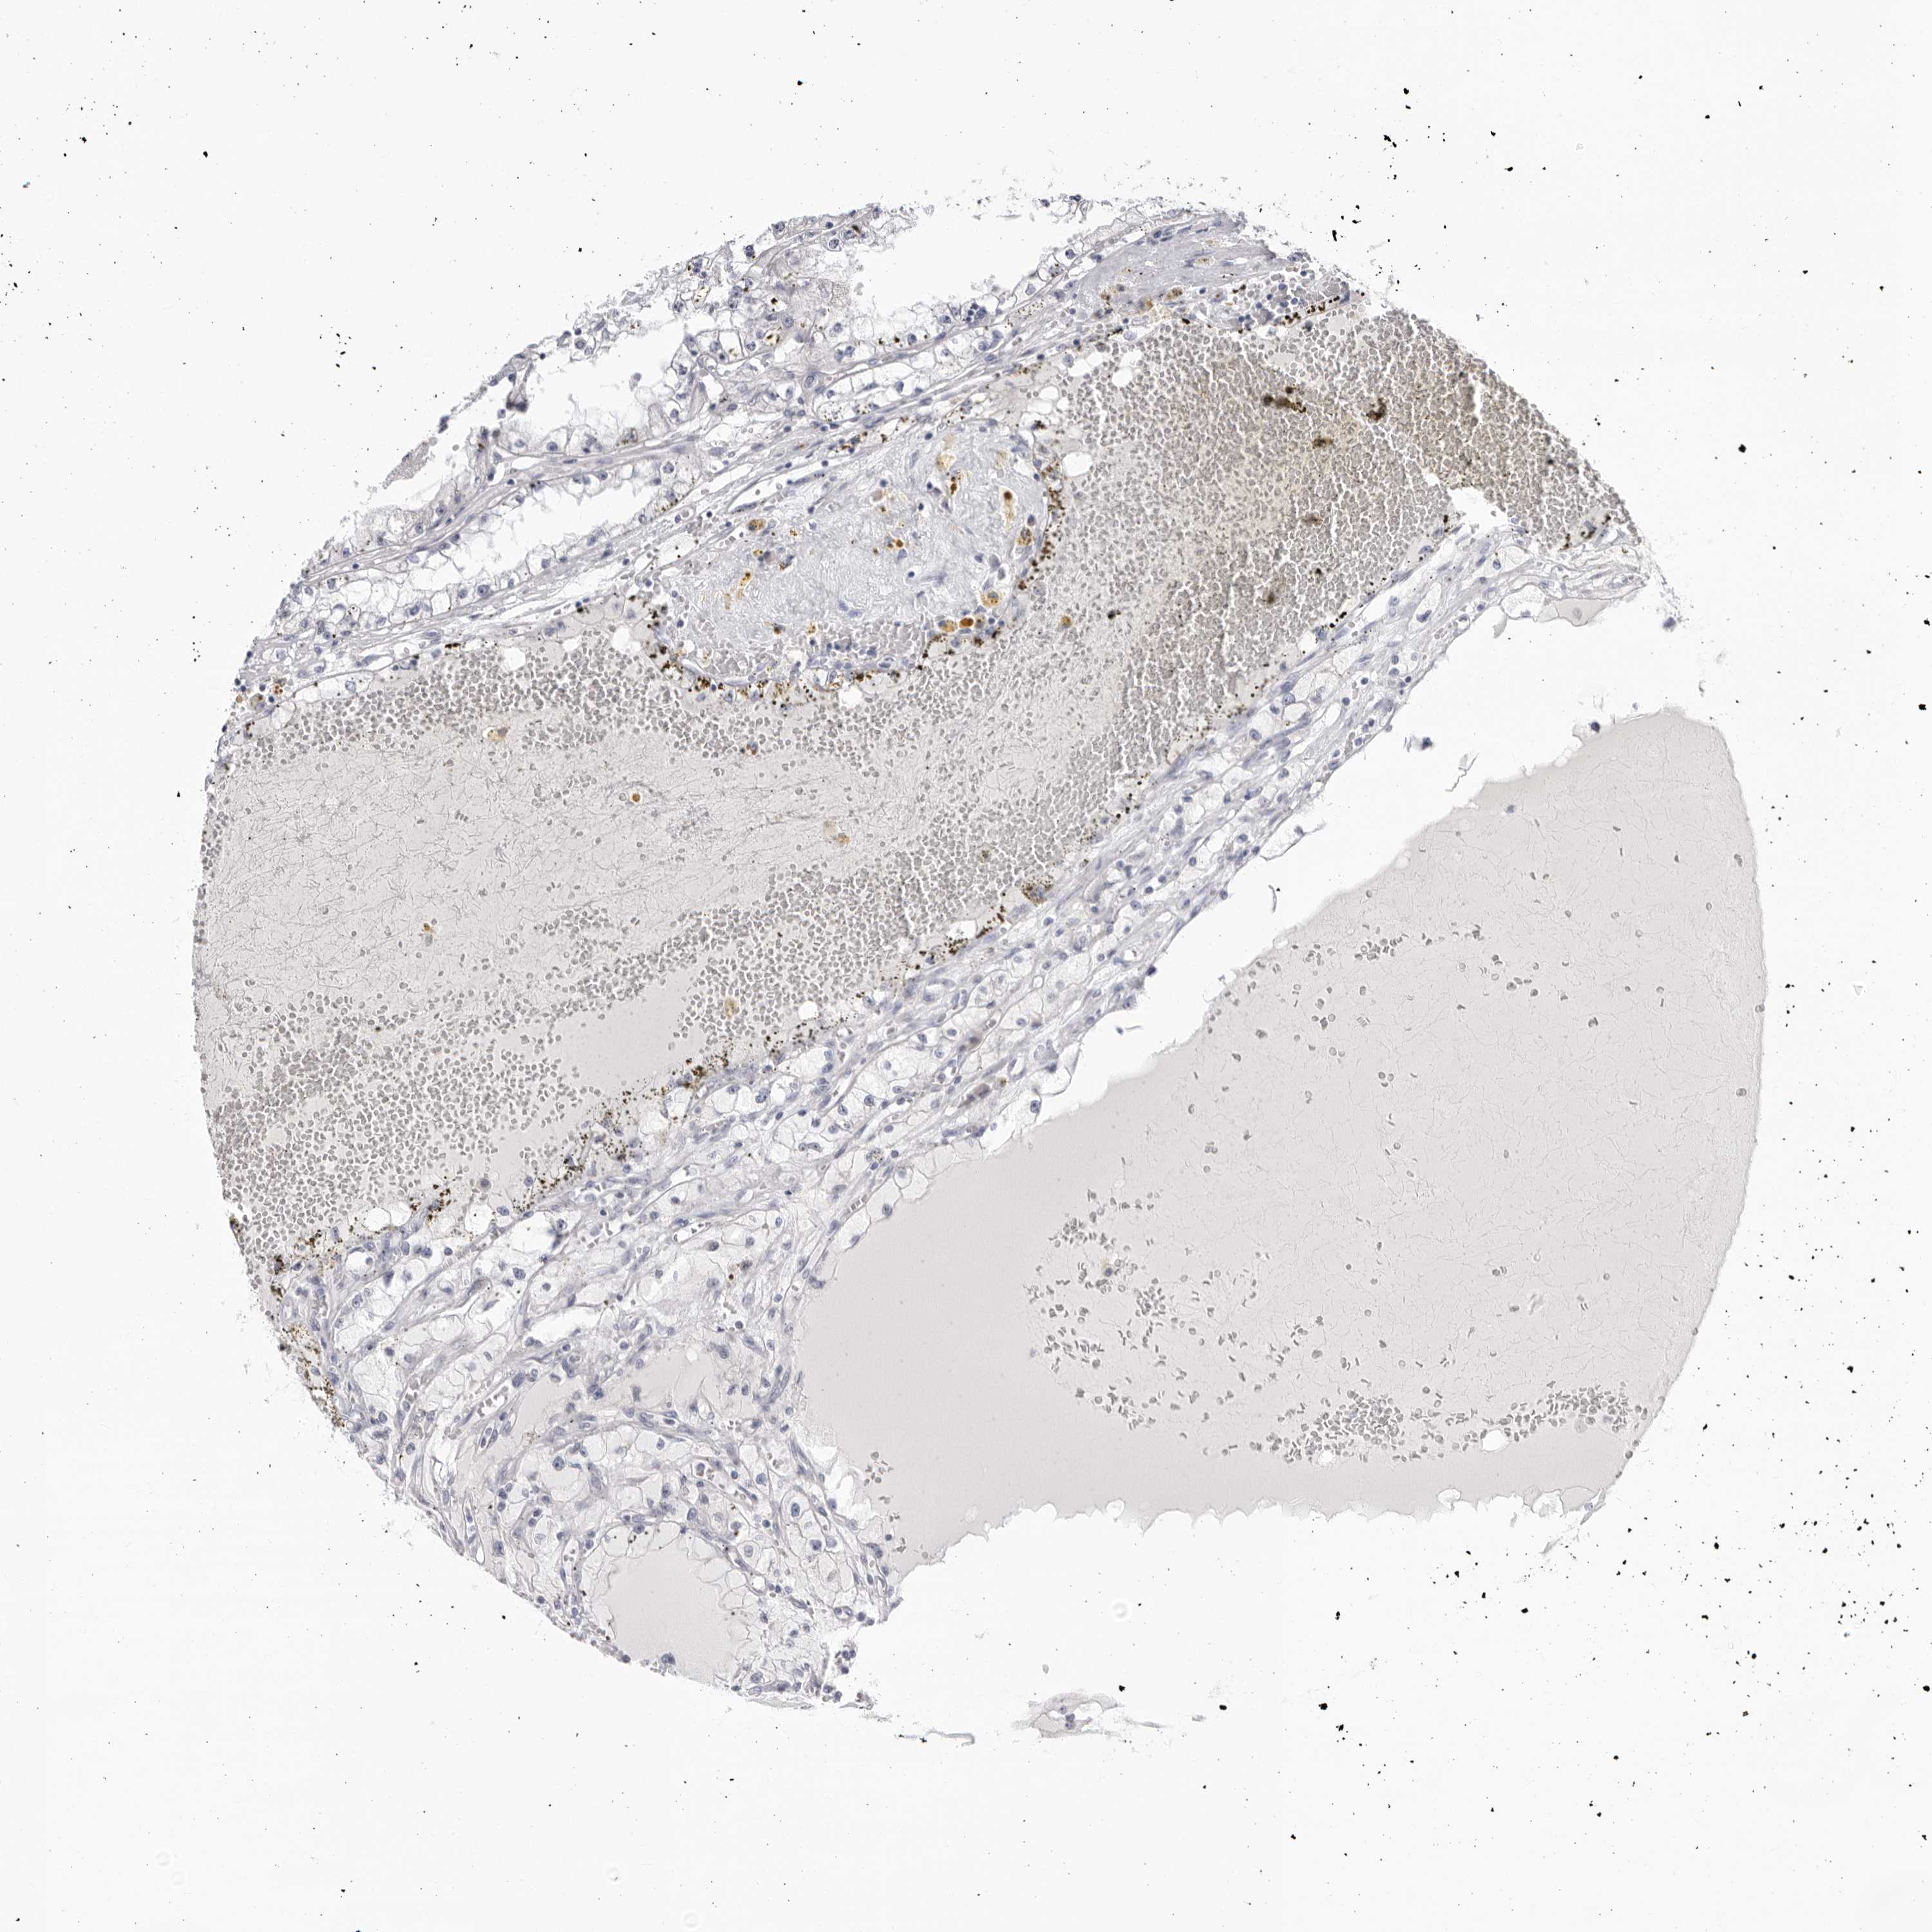

KIDNEY RENAL CLEAR CELL CARCINOMA (VALIDATION) - Interactive survival scatter ploti

The Survival Scatter plot shows the clinical status (i.e. dead or alive) for all individuals in the patient cohort, based on the same data that underlies the corresponding Kaplan-Meier plots. Patients that are alive at last time for follow-up are shown in blue and patients who have died during the study are shown in red.

The x-axis shows the expression levels (FPKM) of the investigated gene in the tumor tissue at the time of diagnosis. The y-axis shows the follow-up time after diagnosis (years). Both axes are complimented with kernel density curves demonstrating the data density over the axes. The top density plot shows the expression levels (FPKM) distribution among dead (red) and alive patients (blue). The right density plot shows the data density of the survived years of dead patients with high and low expression levels respectively, stratified using the cutoff indicated by the vertical dashed line through the Survival Scatter plot. This cutoff is automatically defined based on the FPKM cutoff that minimizes the p-score. The cutoff can be changed by dragging the vertical line or by entering a cutoff value in the square labeled "Current cut-off".

Under the Survival Scatter plot the p-score landscape (black curve; left axis) is shown together with dead median separation (red curve; right axis). Dead median separation is the difference in median mRNA expression between patients who have died with high and low expression, respectively. It is calculated as follows: median FPKM expression of dead patients with high expression - median FPKM expression of dead patients with low expression. This is intended to aid the user in visually exploring custom cutoffs and the associated p-scores and dead median separation.

Individual patient data is displayed and can be filtered by clicking on one or more of the category buttons on the top of the page. Categories describing expression level and patient information include: high, low, alive, dead, female, male and tumor stages. The scale of the x-axis can be toggled between linear and log-scale by clicking on the "x log" button. Mouse-over function shows TCGA ID, patient information and mRNA expression (FPKM) for each patient.

& Survival analysisi

Kaplan-Meier plots summarize results from analysis of correlation between mRNA expression level and patient survival. Patients were divided based on level of expression into one of the two groups "low" (under cut off) or "high" (over cut off). X-axis shows time for survival (years) and y-axis shows the probability of survival, where 1.0 corresponds to 100 percent.

Survival analysis data not available.

TCGA RNA samplesi

RNA-seq data is reported as average FPKM (number Fragments Per Kilobase of exon per Million reads), generated by the The Cancer Genome Atlas (TCGA) .

Normal distribution across the dataset is visualized with box plots, shown as median and 25th and 75th percentiles. Points are displayed as outliers if they are above or below 1.5 times the interquartile range. FPKM values of the individual samples are presented next to the box plot.

Average pTPM 0.0

Number of samples 100